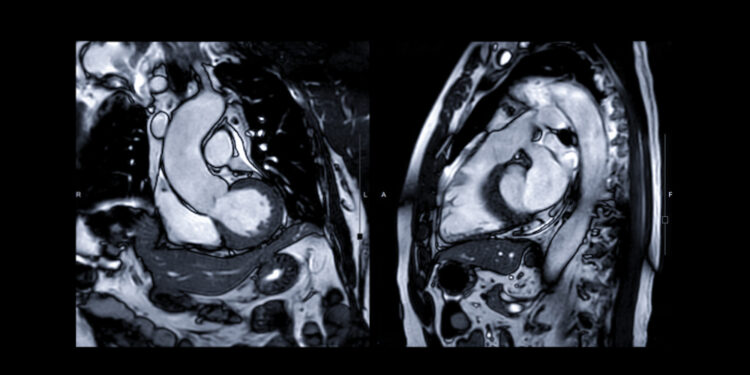

Kaip nustatoma įgimta aortos anomalija?

Iškart po gimimo gydytojai apžiūri naujagimius, ieškodami galimų širdies ydų. Kraujyje matuojamas deguonies kiekis – jei jo per mažai, įtariamas širdies defektas. Klausantis širdies fonendoskopu dažnai išgirstami ūžesiai.

Kokie tyrimai atliekami?

- Širdies echoskopija (echokardiograma).

- Elektrokardiograma (EKG).

- Krūtinės ląstos rentgenograma.

- Kompiuterinė širdies tomografija.

- Kraujo tyrimai.

- Širdies kateterizacija.